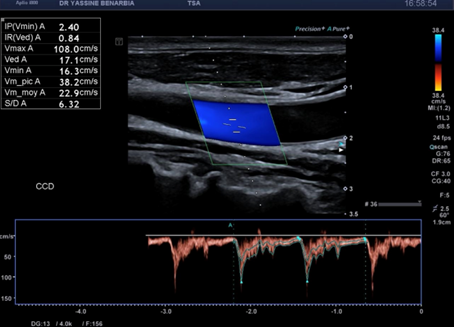

Du côté droit, l'examen met en évidence une dissection du tronc brachiocéphalique (TABC) avec présence d'un faux chenal circulant. Le flap intimal est clairement visible en mode B, séparant le vrai chenal du faux chenal. Au Doppler couleur, on observe un double flux avec des vélocités différenciées : le vrai chenal présente un flux rapide (codé en bleu qui s’éloigne de la sonde) tandis que le faux chenal montre un flux plus lent (codé en rouge qui se rapproche de la sonde).

Cette dissection s'étend à la carotide commune droite proximale. Le Doppler pulsé dans le vrai chenal montre un spectre triphasique conservé avec une vélocité maximale de 108,0 cm/s (normale) et un index de résistivité de 0,84 confirmant l'absence de retentissement hémodynamique. L'artère sous-clavière droite et l’artère vertébrale restent perméables avec des flux normaux au doppler.

Les signes retrouvés à l'échographie-Doppler sont : flap intimal mobile visible en mode B séparant vrai et faux chenal, double lumière artérielle en coupe transversale et longitudinale, flux différenciés au Doppler couleur (vélocités élevées dans le vrai chenal, flux plus lent dans le faux chenal), et spectre Doppler pulsé conservé dans le vrai chenal (triphasique ou biphasique).

Les critères de stabilité à surveiller sont : taille du faux chenal inchangée, flux conservé dans le vrai chenal avec vélocimétrie normale (Vmax < 125 cm/s), absence d'extension de la dissection, absence de thrombose progressive, et absence de dilatation anévrysmale.